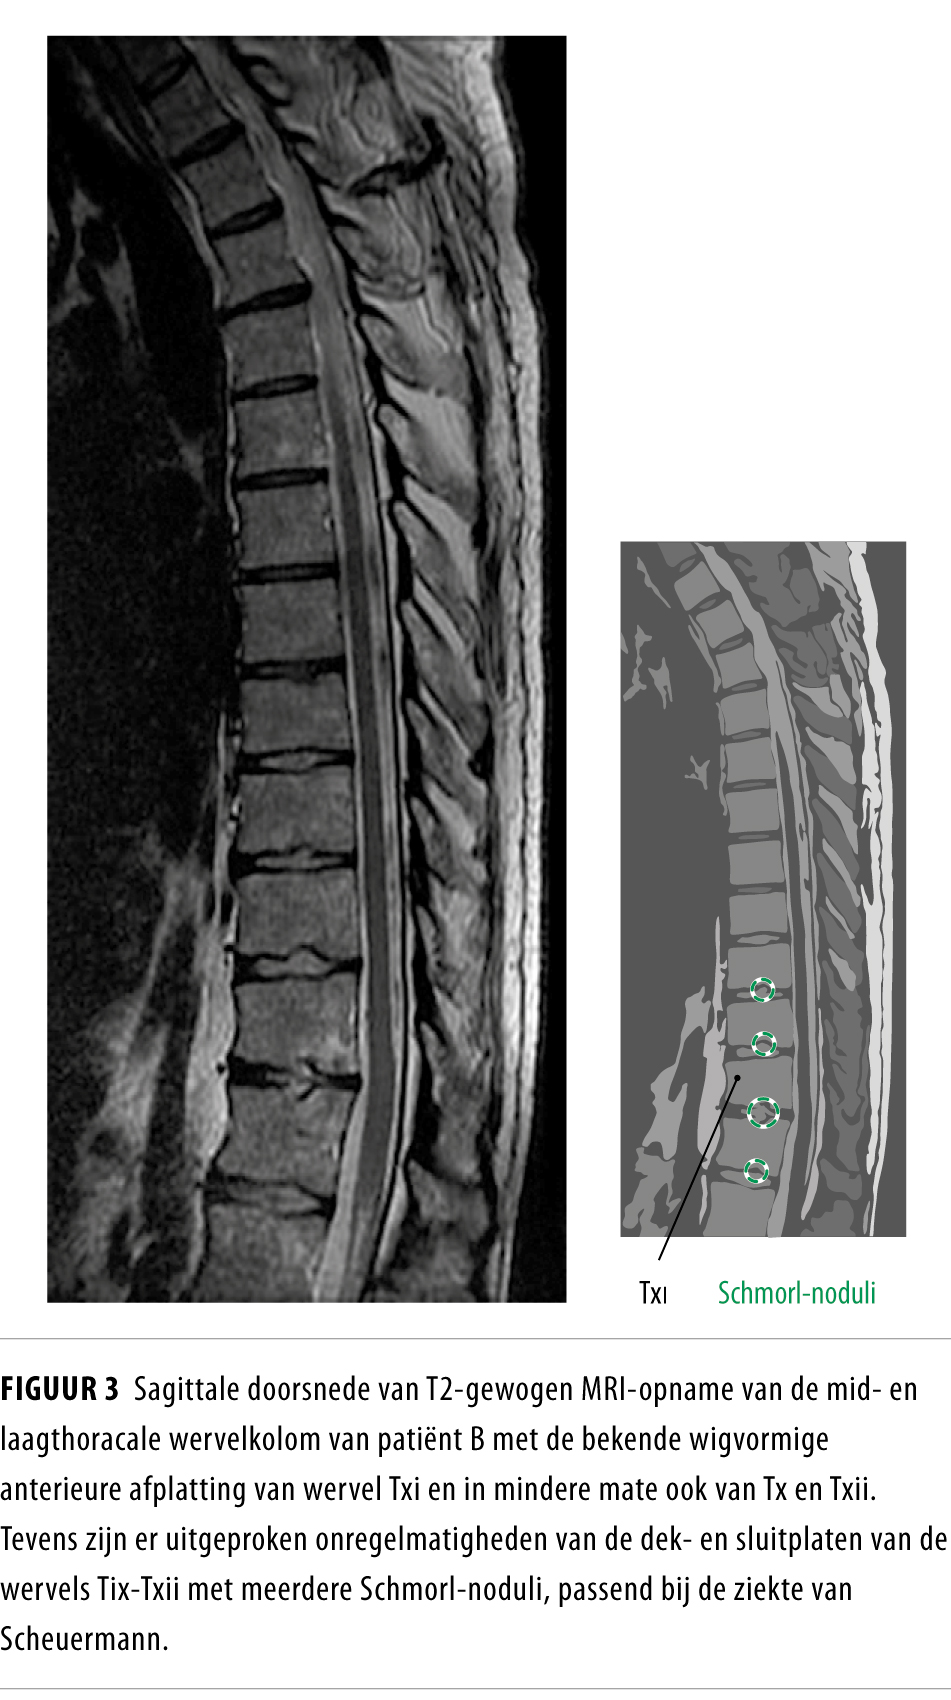

From www.ntvg.nl

Osteoporotische wervelfracturen of ziekte van Scheuermann? Nederlands Rug Ziekte Van Scheuermann Dit komt met name voor wanneer er een forse kromming is en er een zichtbaar ronde rug ontstaat. Pijnscheuten in de bovenrug bij. De ziekte ontstaat in de pubertijd, vooral bij. Bij scheuermann is de wervelkolom kromgegroeid, wat een extreem verkromde bovenrug veroorzaakt, ook wel (hyper)kyfose genoemd. De ziekte van scheuermann is een aandoening aan de wervelkolom. Wat is de. Rug Ziekte Van Scheuermann.